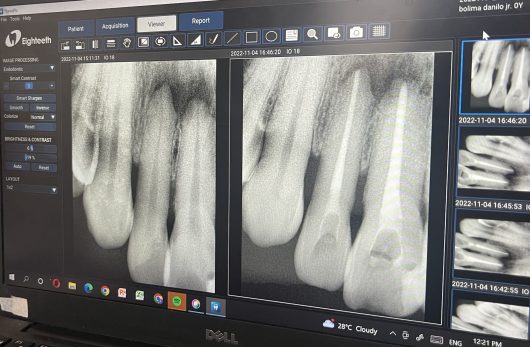

Preparation for oral surgery involves several steps: first, undergo a detailed dental examination with X-rays to assess the condition of your teeth and jaw.

Root canal treatment is a dental procedure used to repair and save infected or damaged teeth. It is usually recommended when the pulp is infected or damaged and cannot be repaired.

Root canal treatment can be considered a form of oral surgery when it involves complex procedures to remove infected or damaged pulp from the inside of the tooth.

It’s necessary when there’s inflammation or infection within the roots of a tooth. This treatment aims to save the tooth and alleviate dental pain, preventing further infections and complications.